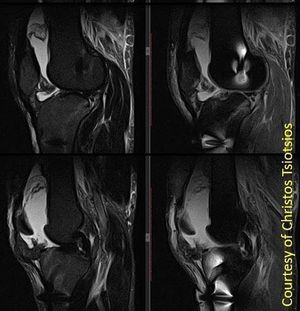

Sagittal PD-w TSE with chemical fat saturation (right) shows heterogeneous fat suppression due to magnetic field inhomogeneities. Sagittal T2-w STIR (left) provides robust fat suppression. Moreover, susceptibility artifacts are less prominent on old-school STIR images. It is very important that Radiographers be aware of the advantages and disadvantages of the various fat suppression techniques, in order to select the most appropriate technique for each particular situation in clinical practice. Images courtesy of Christos Tsiotsios.